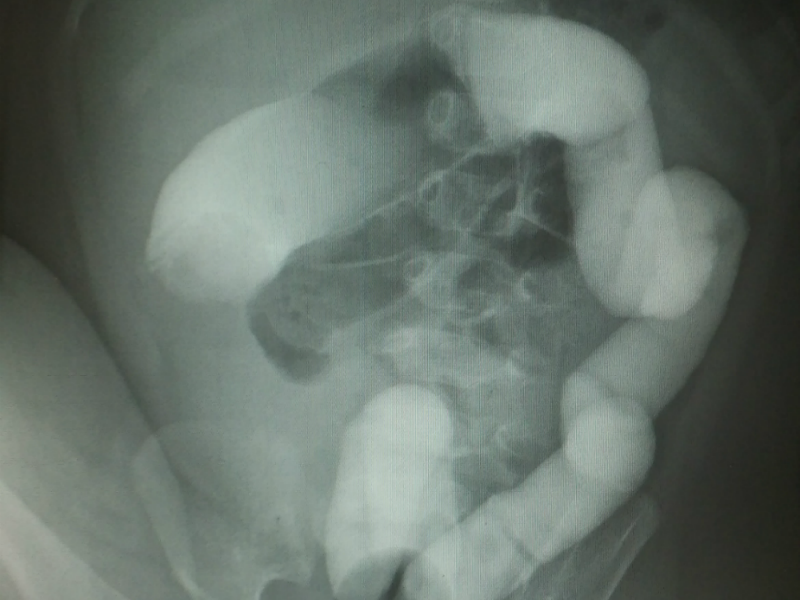

이 질환은 대부분 6개월에서 2세 사이 건강한 소아에서 갑자기 발생합니다. 보통 심하게 자지러지는 복통이 5~10분 간격으로 반복적으로 나타나는 경우가 흔하고 시간이 지나면 구토와 혈변, 그리고 젤리 같은 변을 보는 특징이 있습니다. 장벽에 있는 점액질이 함께 나오는 것이겠죠. 진단은 초음파로 장이 겹쳐져 막힌 부분을 확인하는 것이고 치료는 항문을 통해 공기나 조영 물질을 섞은 액체로 장을 밀어내어 펴주는 치료를 하게 됩니다. 간혹 관장 정복에 실패하거나 장천공이 발생하면 수술적 치료가 필요한 경우도 생깁니다.